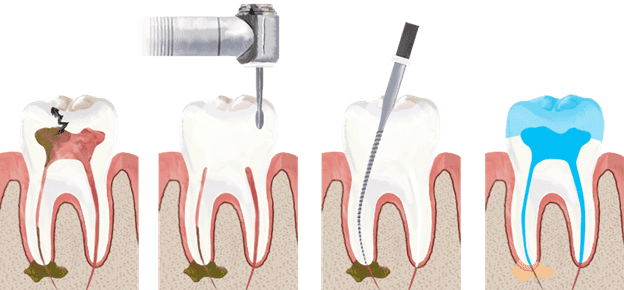

Root canal treatment (also known as endodontic therapy) is a dental procedure used to treat infection or damage in the pulp of a tooth—the soft tissue inside that contains nerves and blood vessels. Instead of extracting the tooth, our expert dentists clean, disinfect, and seal it to preserve your natural tooth structure.

Re-root canal treatment involves cleaning, disinfecting, and resealing the root canals to remove any lingering infection.